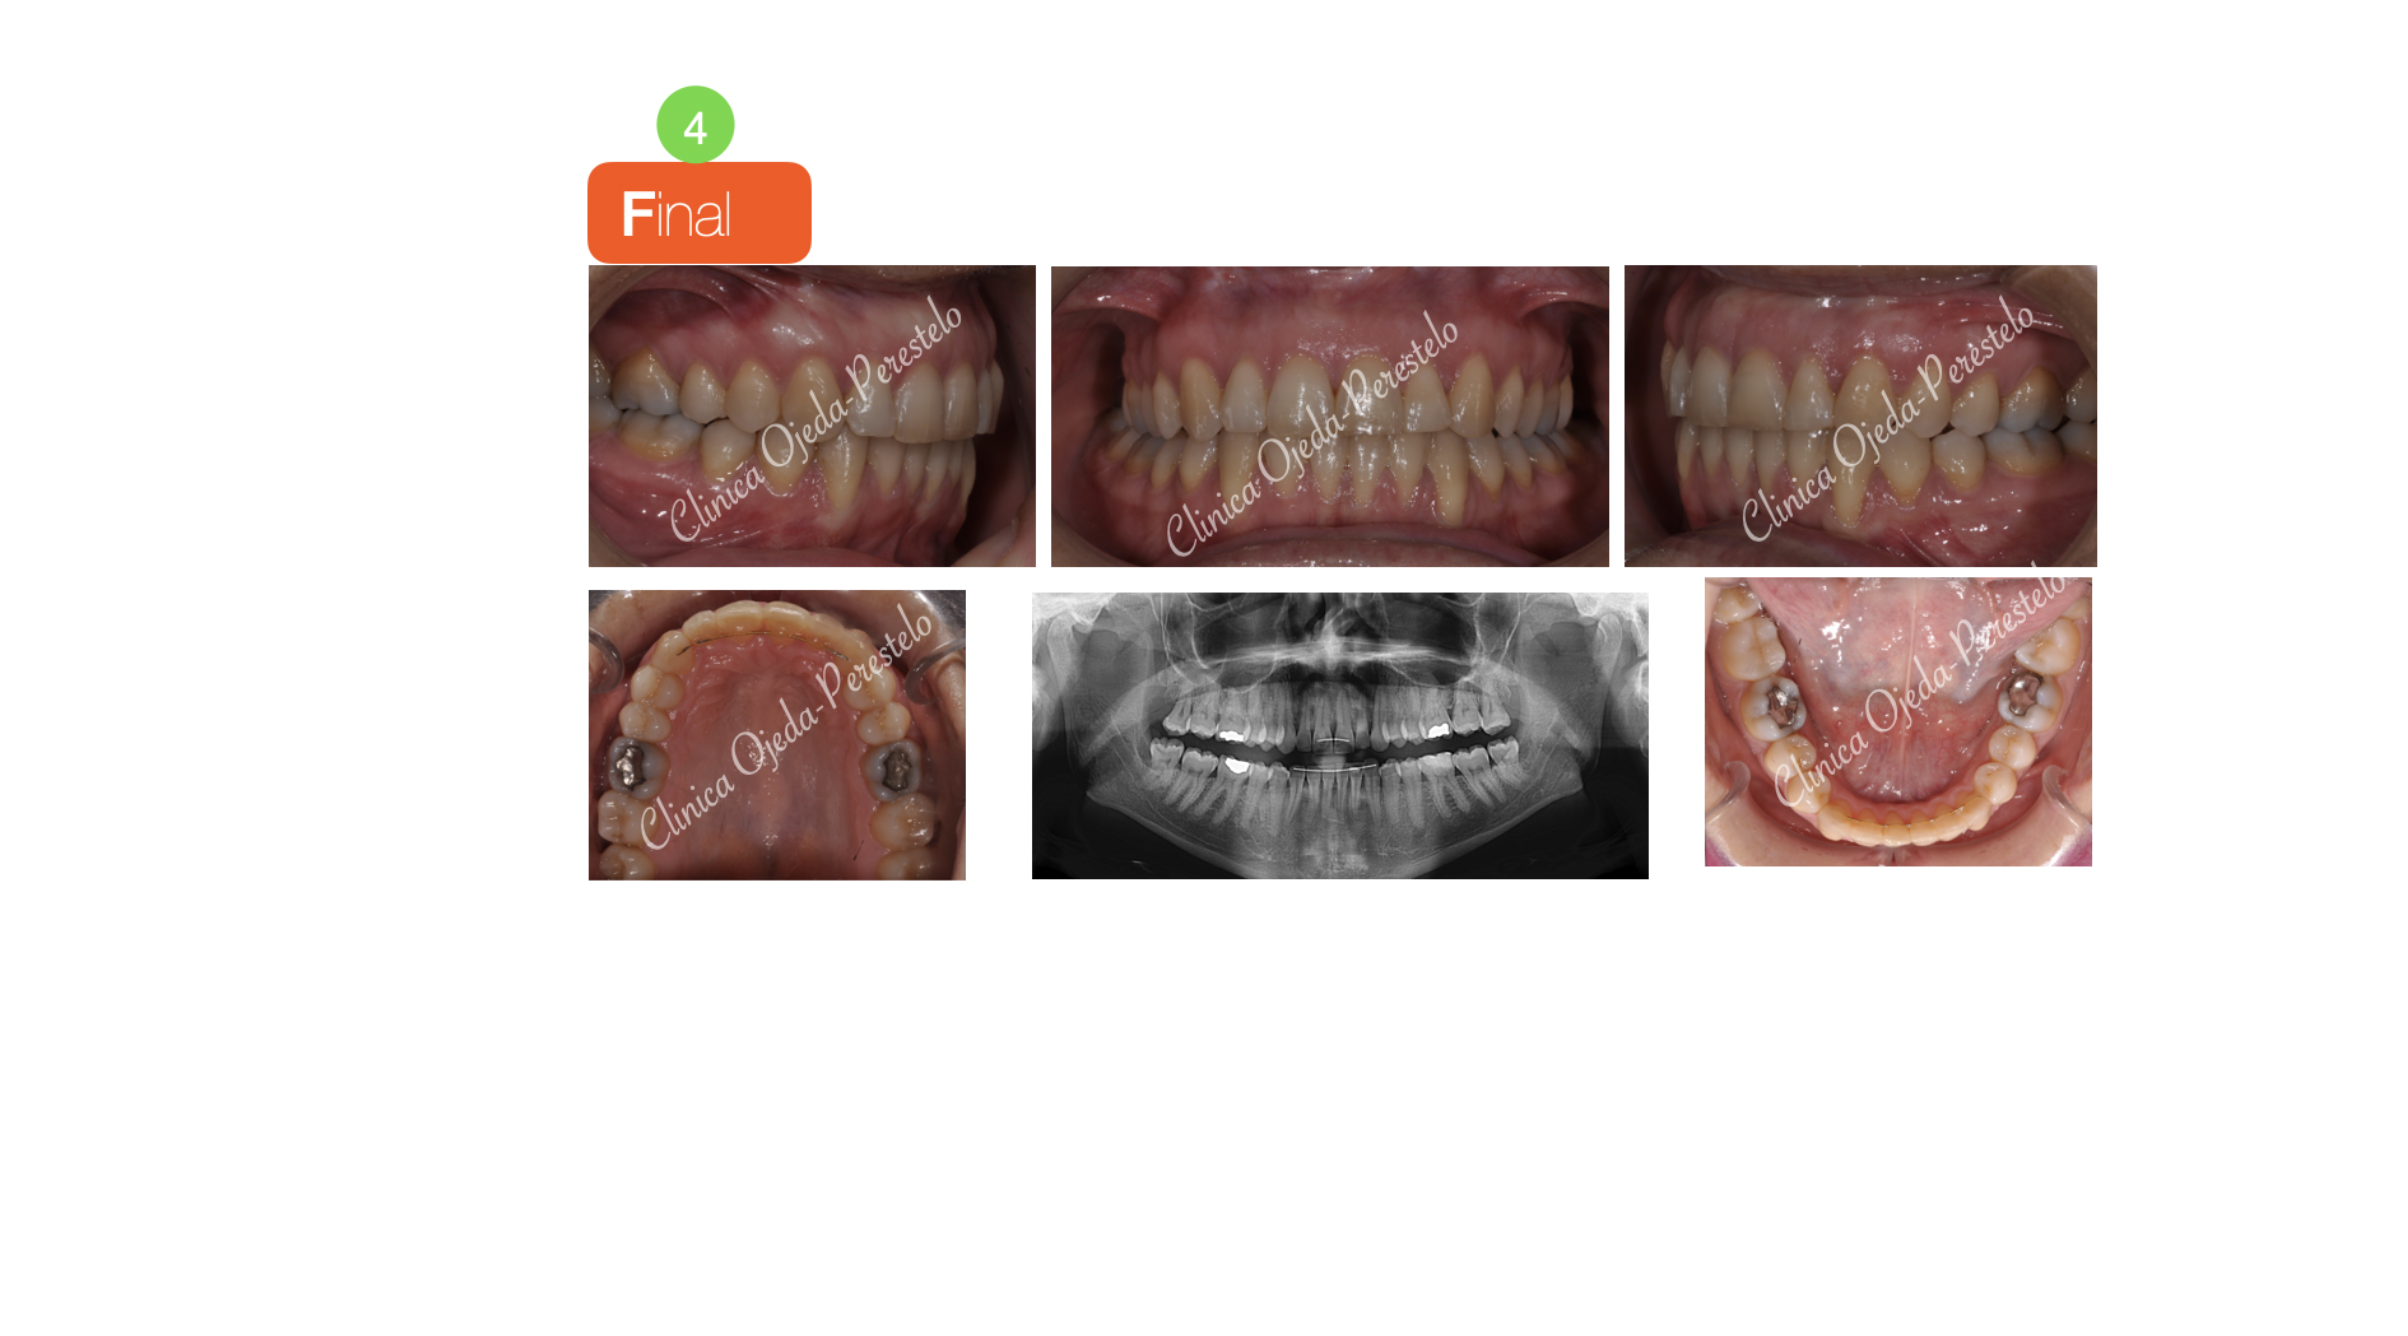

El cierre del diastema y el ordenamiento de las piezas se realizó con Ortodoncia Fija (Sistema Damon).

Quisiéramos destacar la mejora en la sonrisa y la función masticatoria tras finalizar el tratamiento. Presentamos la estabilidad del caso a 10 años estando la paciente pendiente de realizarse un injerto de encía a nivel del 31 y 33.